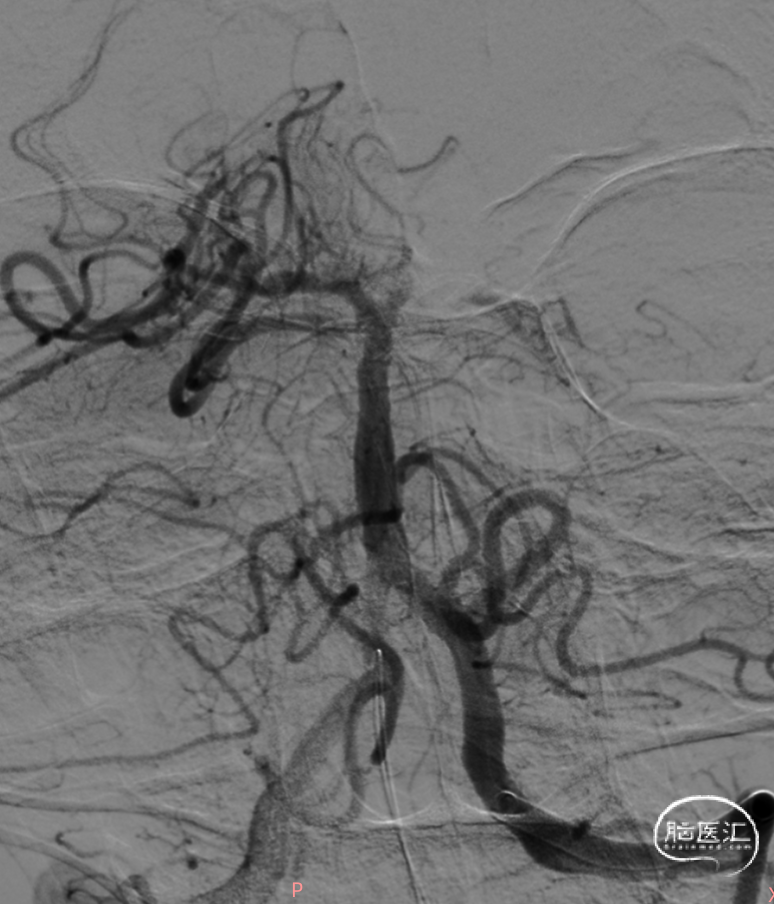

左侧椎动脉造影。

6F 125cm 通桥银蛇®颅内支持导管到位。

6F 125cm 通桥银蛇®颅内支持导管抽吸过程。

负压抽吸2次,基底动脉顶端部分再通,见栓子向双侧大脑后动脉逃逸。